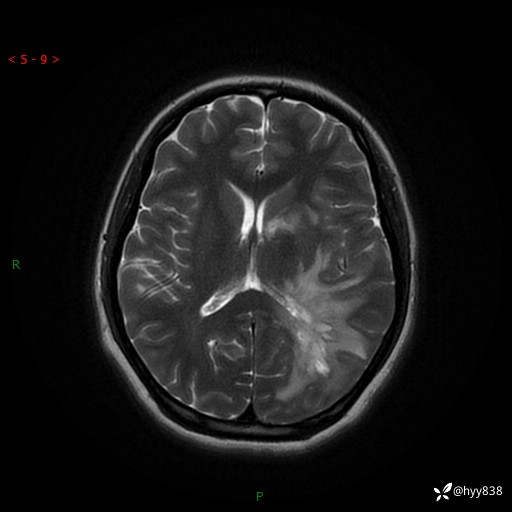

颅脑MRI平扫+增强